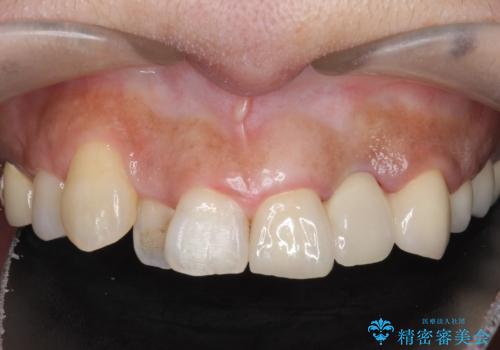

左上2番目の歯は歯根が破折してため抜歯し、左上123のブリッジによる欠損補綴を行いました。

左上4、5番目の歯は根尖病変を認めたため再根管治療を行い、オールセラミッククラウンによる補綴を行いました。

今回用いたオールセラミッククラウンは、ジルコニアフレームという白い素材の上にセラミックを盛っているため審美性が非常に高いのが特徴です。

またジルコニアは人工ダイヤモンドの材料にも使われているほど高い強度を持っており、そのためオールセラミッククラウンは審美性だけでなく、奥歯やブリッジの補綴も可能とするクラウンです。